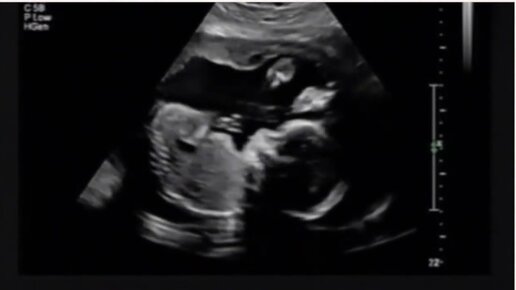

УЗИ на 23 неделе беременности

Медицинский женский центр